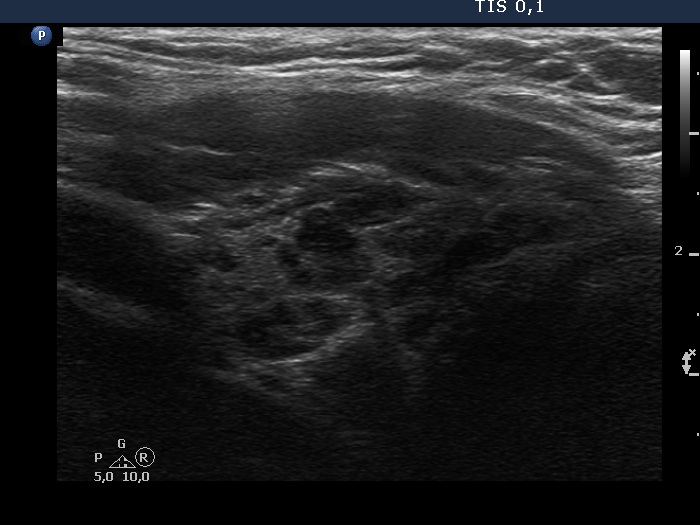

Teamwork - case 201 (ultrasonographic picture 6)

Right lobe, longitudinal view - set to better resolution. The lobe has numerous hypoechoic areas which correspond to more active foci of thyroiditis